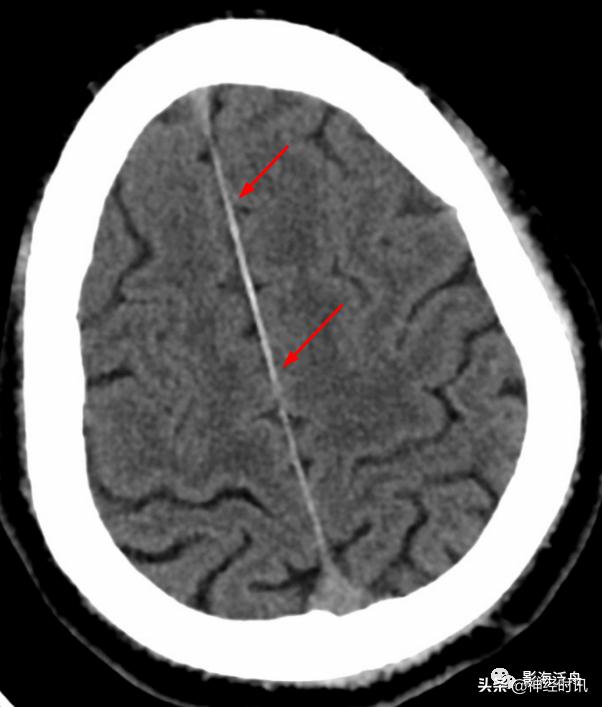

红箭所指的大脑镰局部呈连续的长条状高密度影,容易被误诊为少量蛛血,此系大脑镰局部不完全钙化所致。注意观察密度增高的大脑镰边缘非常光滑、且居中(红箭),与少量蛛血形成的偏密征、边缘毛糙等征象恰好相反。

间断性的大脑镰不完全线状钙化(红箭),同样呈边缘光滑、居中改变。